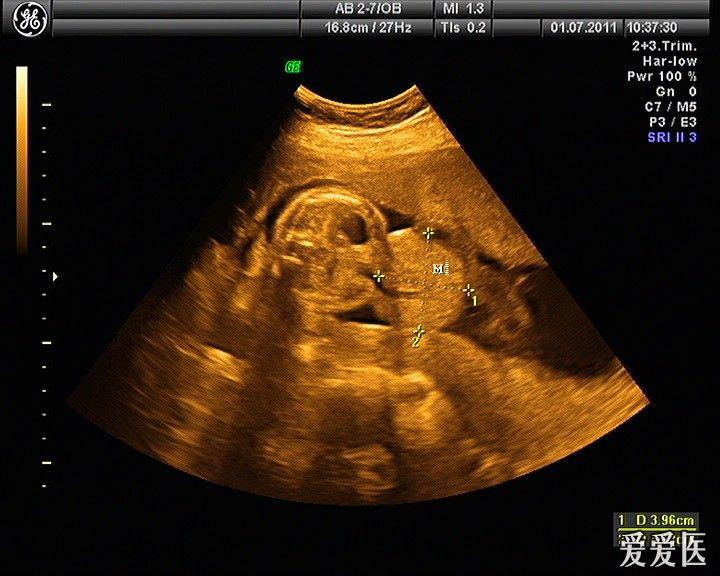

胎儿脐膨出:引产后证实,可惜没有引产后照片